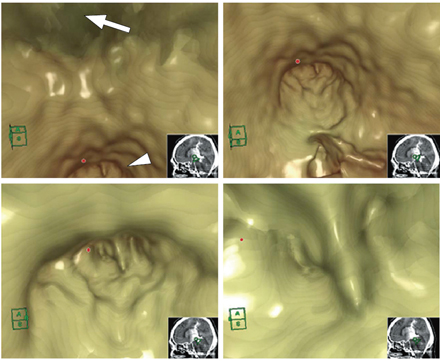

図4 仮想内視鏡画像

仮想内視鏡上で第3脳室底(←)を確認にして,後方の拡大した中脳水道入口部(▲)に接近する動画を作成した。中脳水道の正中に前後に走るseptumがあることと,第4脳室への造影剤の流入ポイント(●)がseptumの左側であることが,術前シミュレーションで確認できた。

図5 手術シミュレーション,仮想内視鏡画像と手術所見の対比

第4脳室をsegmentation(青色)して中脳水道入口部の画像と合成することで,中脳水道と第4脳室の位置関係を術前に検討できた。神経内視鏡手術と比較すると,中脳水道の正中に前後に走るseptum(↑),その左側に薄い癒着膜(▲)の存在を確認できた。中脳水道の正中のseptumの左右で開窓して第4脳室と交通をつけた。